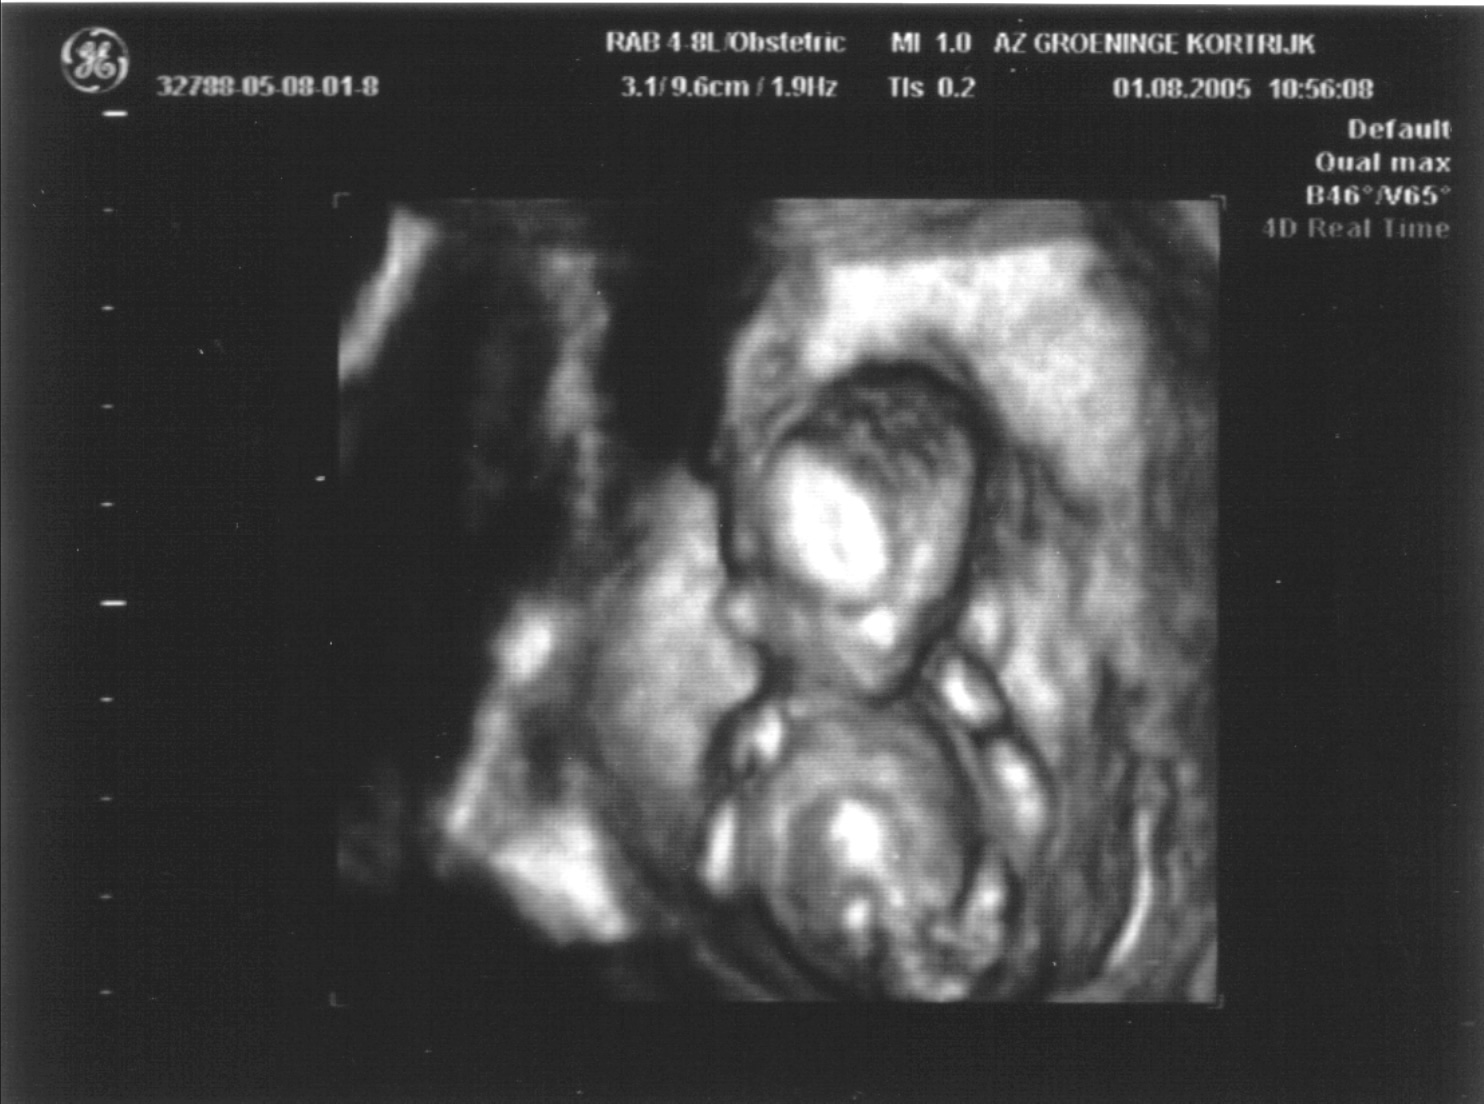

Aangezien onze normale dokter op vakantie was mochten we op 13 weken bij haar vervanger langs, die ons deze mooie 3D echo bezorgde